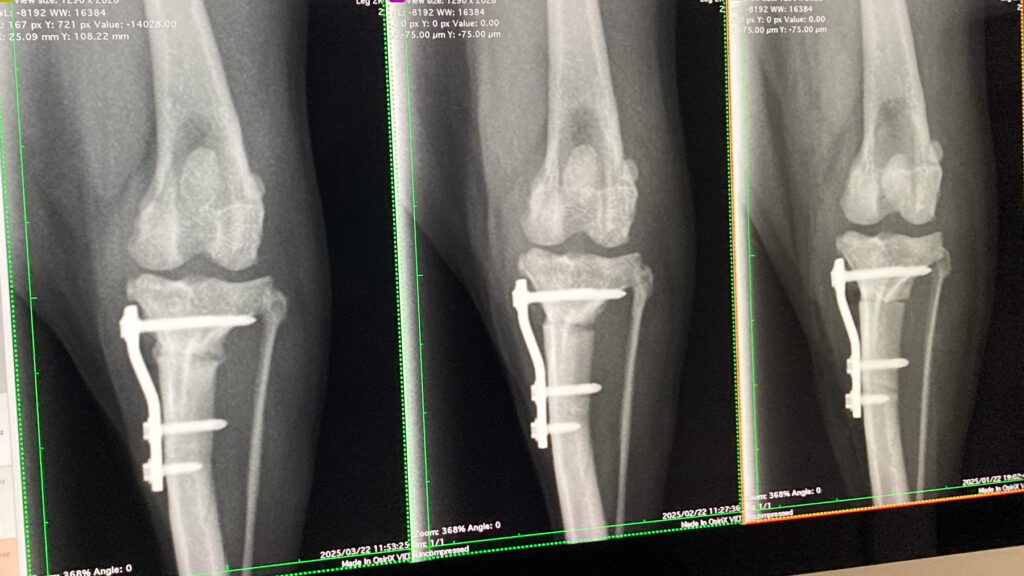

レントゲンのように、大腿骨(太ももの骨)と脛骨(すねの骨)が正常な位置にもどされ、体重をかけても大丈夫なようになりました。

定期的な通院

退院したあと、また2週間後に診察し様子を伺います。

その後は1ヶ月ごとに通院していただき、レントゲン検査や触診にて様子を確認します。

通院のたびに、気になることや不安に思っていることなどあればご相談を受け今後の方針を話し合います。

前面からの撮影

膝蓋骨の位置が真ん中に安定しており、だんだんと上に上がっていく様子が分かる。